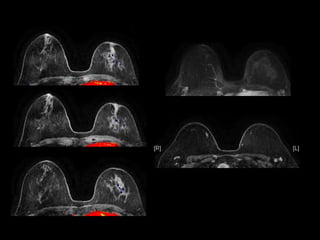

Dr. Ana Lourenco

HISTORY

• 36 yo female 30.5 weeks pregnant

• Referred with ‘multiple fetal anomalies’ for

fetal ultrasound

LUS – Cephalic

POSTNATAL BABYGRAM

• What are the findings?

• What is the diagnosis?